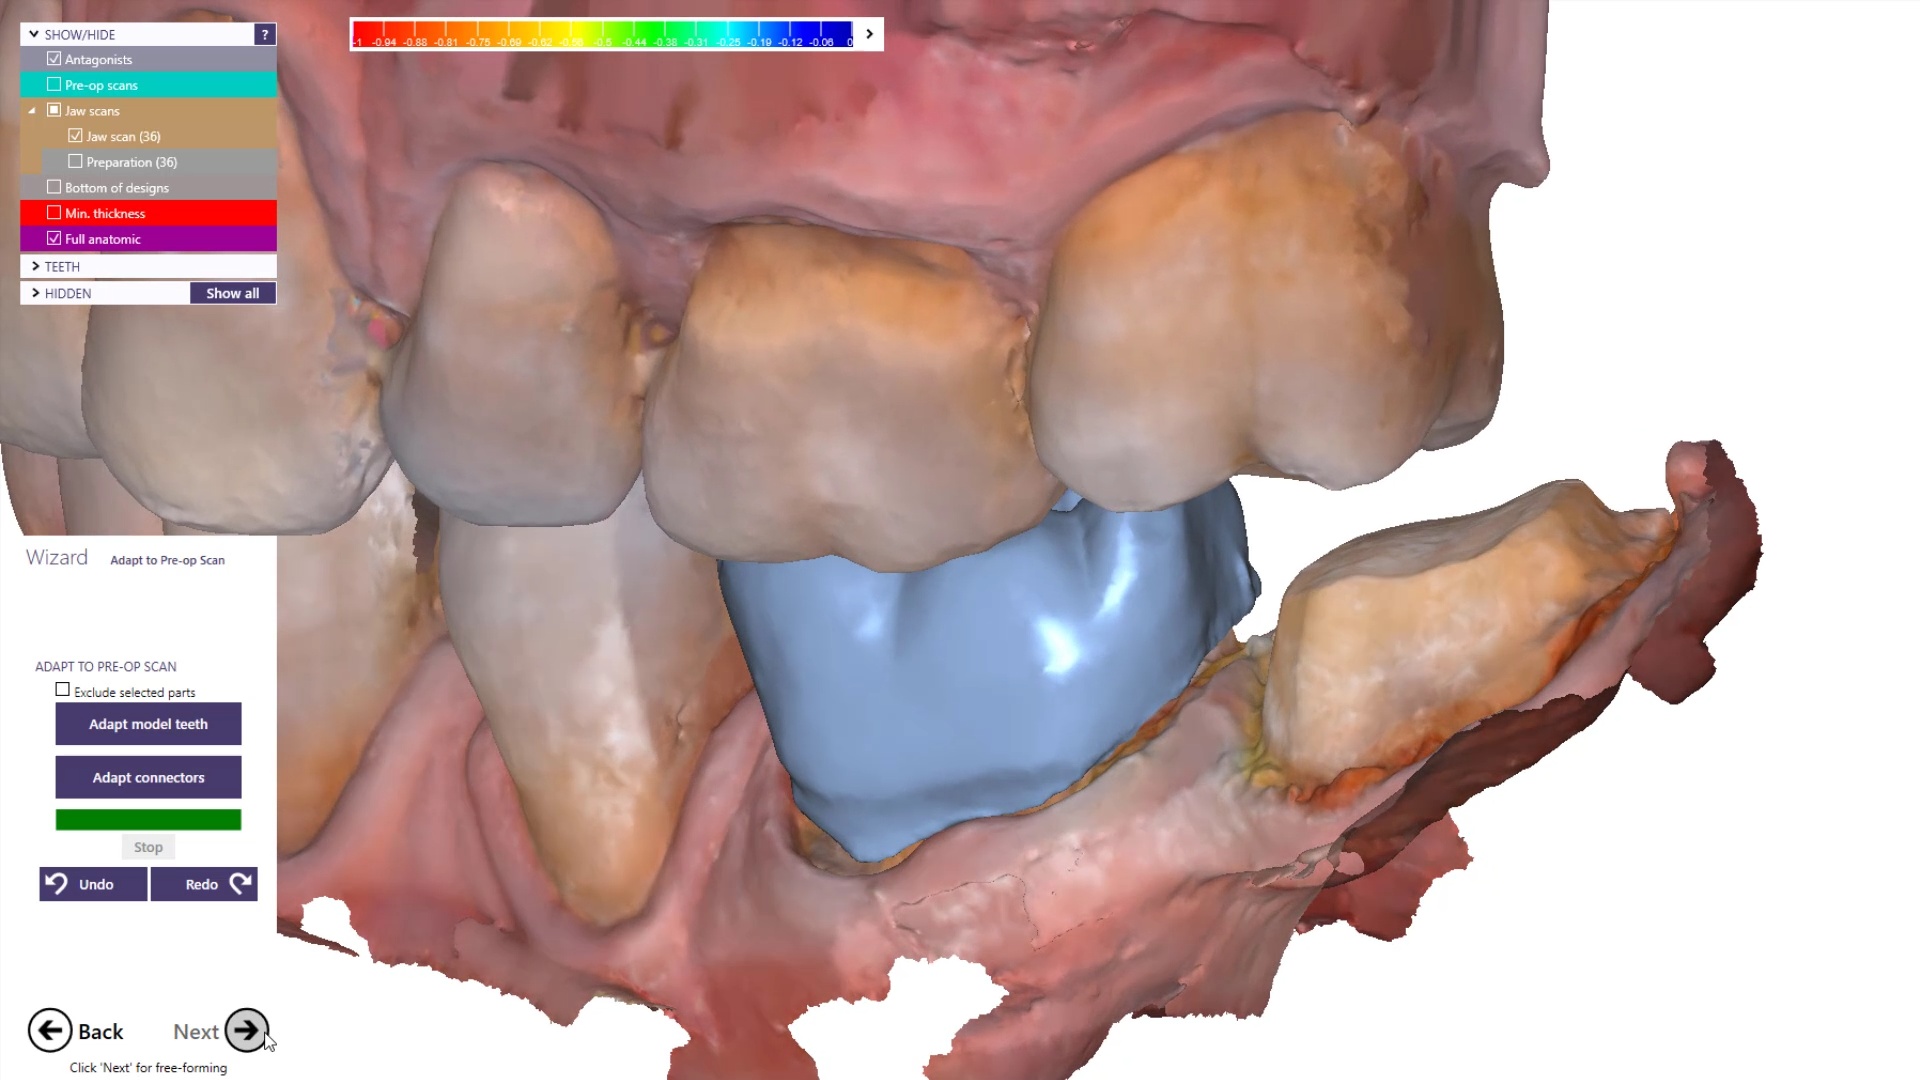

To manage the contact between the two crowns, there are many advanced applications. Here is a simple explanation of how we use the prep model from case 1 as the pre-op model for case two. Since the second molar in case 1 made contact with the distal wall of the first molar, when we design the crown for the first molar in case 2, all we have to do is make sure the distal wall is flush to the pre-op. This guarantees us a contact between the two. There are lots of shortcuts to this puzzle once you get the basics of digital impressions under your belt.

We quickly printed these same models and crowns just for demonstration purposes